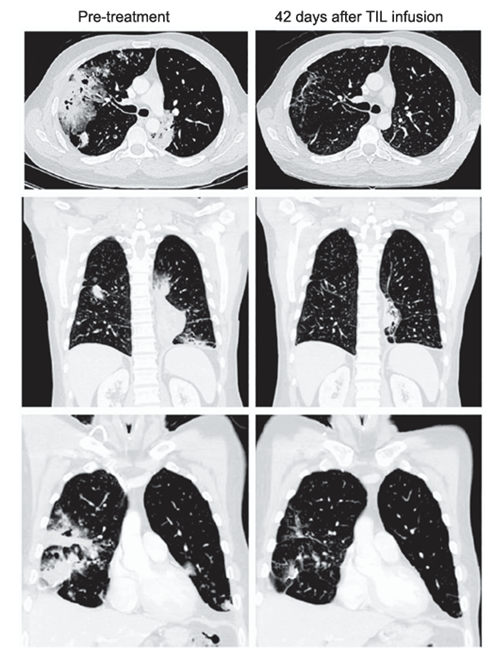

01 晚期肺癌接受TIL细胞疗法,42天后肿瘤大幅度缩小! 目前,免疫检查点抑制剂(ICIs)疗法已经为转移性非小细胞肺癌(mNSCLC)的治疗带来革命性突破。然而,该疗法对PD-L1阴性患者以及存在ICIs原发性或获得性耐药的患者疗效有限。因此,探究肿瘤浸润淋巴细胞(TILs)细胞疗法在mNSCLC治疗中的应用价值具有迫切的临床需求。 美国俄亥俄州立大学癌症中心专家团队曾在Cancer Discovery杂志发布了一项TIL细胞疗法的临床数据[1]。结果显示:对于经过多重治疗失败,尤其是免疫检查点抑制剂(ICIs)耐药的晚期mNSCLC患者,TIL细胞疗法治疗的客观缓解率(ORR)达21.4%(6/28),有接近80%的患者(79.2%,19例)的患者实现肿瘤负荷下降。其中,还有1例患者更是达到完全缓解(CR),展现出TIL细胞疗法强大的抗癌潜力。 尤为值得关注的是其中一位患者,他是一名41岁、携带KRAS G12D突变的IV期粘液性肺腺癌男性患者,其肿瘤突变负荷(TMB)仅为3.3mut/Mb,且PD-L1表达为0%。根据患者的基因突变情况,他没有可以接受的靶免治疗方案,免疫治疗提示获益较低,患者一度陷入了“无药可治”的阶段。不过,转机是他在接受TIL细胞疗法治疗42天后,依据标准评估,其部分缓解(PR)率高达81%,这一突破性疗效为特定基因分型的肺癌患者带来了新的治疗希望。 TIL细胞疗法治疗42天前后的影像学资料,显示患者获益明显 图源:aacrjournals.org 02 肿瘤浸润淋巴细胞(TILs)治疗的优势 ① 特异性强:实体肿瘤肿瘤微环境复杂,异质性高。TILs是多克隆的肿瘤特异性杀伤型T细胞,可靶向多个肿瘤抗原,能够克服肿瘤异质性问题,具备长效杀伤肿瘤细胞的优势。 03 接受TIL细胞治疗,多名晚期癌症患者4-6周快速控制肿瘤! 在今年的AACR会议(2025年美国癌症研究协会)上,TIL细胞疗法在实体瘤的人体试验结果也交出了一份令人瞩目的答卷[2]。NCT06145802试验中,TIL细胞疗法展现出优异的安全性与初步抗肿瘤活性。其中,一例难治性宫颈癌患者在接受TIL细胞疗法仅4周后,便达到完全缓解(CR)状态。治疗前,该患者阴道内有一个24mm的转移性病灶,在第38周的放射影像检查中已实现100%缩小,并且治疗反应持续了超过了一年,至今还在保持中。 另外还有一名卵巢癌患者,之前接受过9线的全身治疗,已经穷尽所有治疗方式,抱着一丝希望接受了TIL细胞疗法,然而奇迹的是在输注后6周就已经达到确认的部分缓解(PR),而且缓解持续也直接超过一年。目前的数据显示75%的患者OS接近一年,这一突破性成果为实体瘤治疗带来新的曙光! 结 语 肿瘤浸润淋巴细胞(TILs)具有特异性强、安全性高及浸润性好的优势。目前的临床研究来看,除了黑色素瘤,在肺癌、卵巢癌、宫颈癌等癌种中也取得了令人瞩目的临床疗效。